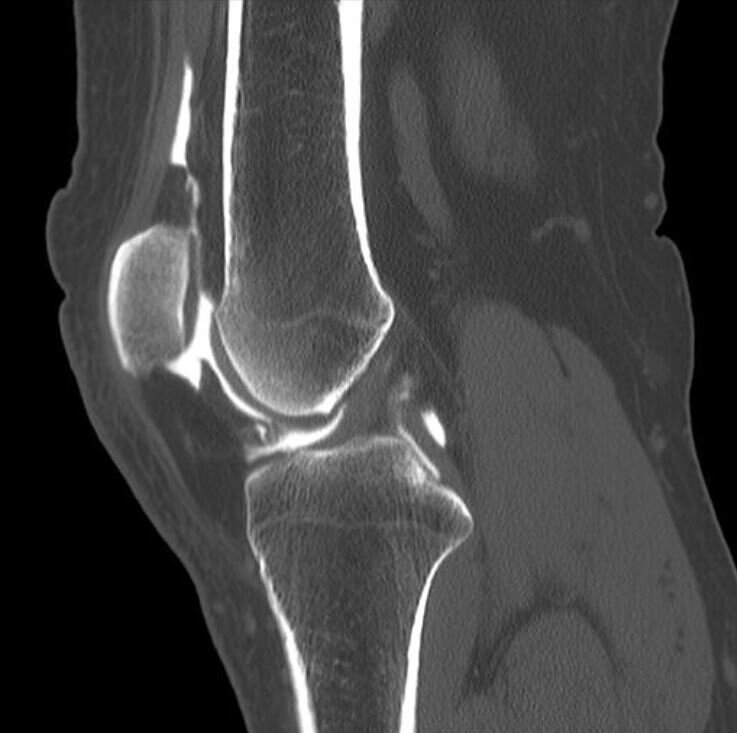

КТ коленного сустава является рентгенологическим исследованием области колена на специальном томографе, который делает в процессе диагностики несколько сотен срезов. Этот метод хорошо показывает костные ткани и окружающие структуры. В зависимости от мощности томографа установка способна делать сканы с шагом до 1 мм, формировать из них томограммы и выводить на экран компьютера в 3D-формате. Пройти компьютерную томографию коленного сустава в клиниках Санкт-Петербурга может любой человек, если обратится к хирургу, ревматологу или ортопеду-травматологу за направлением. Также имеется возможность записаться на обследование самостоятельно при помощи нашего Общегородского центра записи на МРТ и КТ. Наши специалисты помогут выбрать наиболее подходящий медицинский центр с выгодными ценами на КТ коленного сустава. В СПб есть ряд медицинских клиник, предлагающих такое обследование со скидкой в ночное время. КОГДА НУЖНО СДЕЛАТЬ КТ КОЛЕННОГО СУСТАВА?  К проведению компьютерной томографии колена

КТ костей и тканей колена может успешно показать различные изменения костных структур сустава, количество суставной жидкости и скопление крови, аномалии развития, деструктивные процессы. С помощью МСКТ можно выявить признаки остеомиелита, остеофиты, опухолевые заболевания костей, новообразования (как доброкачественные, так и раковые).

С помощью данных детальных томограмм компьютерной томографии коленного сустава у врачей есть возможность оценить:

• костно-травматические изменения;

• выпот в области крестообразных связок;

• сужение суставной щели;

• изменения суставных поверхностей;

• признаки дегенеративных изменений в мениске;

• целостность крестообразных и коллатеральных связок;

• дистрофические изменения в хрящевой ткани.